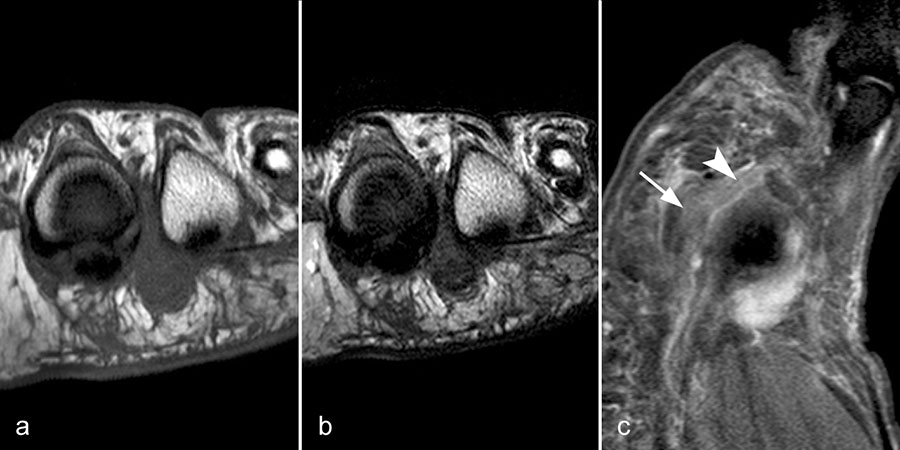

Typische Gichtmanifestation an der Großzehe mit Tophusstachel (Pfeil) und großem Tophus, in welchem Uratablagerungen identifiziert werden können (Pfeilspitze). T1-gewichtete Sequenz vor (a) und nach (b) Kontrastmittelgabe, letztere mit Fettsuppression.

Abbildung 15

Dies erst recht, wenn diese Arthritis am Großzehen­grundgelenk auftritt (Abb. 15). In diesen Fällen sollte man den Verdacht auch dann aufrechterhalten, wenn die MRT nur eine unspezifische Entzündung zeigt und die Harnsäurewerte, die starken Schwankungen unterliegen können, nicht erhöht sind.

Spezifische MR Befunde finden sich erst bei der chronischen Gicht, wenn sich in T2 sehr signalarme Kristallablagerungen und Gicht-Tophi bilden. Letztere führen dann häufig zu den aus der Röntgendiagnostik bekannten gelenkfernen Erosionen.

Abbildung 15: Typische Gichtmanifestation an der Großzehe mit Tophusstachel (Pfeil) und großem Tophus, in welchem Uratablagerungen identifiziert werden können (Pfeilspitze). T1-gewichtete Sequenz vor (a) und nach (b) Kontrastmittelgabe, letztere mit Fettsuppression.